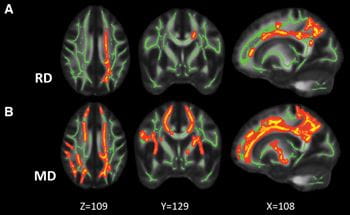

MRI imageThe Advanced Imaging Research group is a joint program between the Stark Neurosciences Research Institute and the Indiana Institute of Biomedical Imaging Sciences at the Indiana University School of Medicine. The central mission of the Advanced Imaging Research program is threefold: to advance magnetic resonance imaging (MRI) and positron emission tomography (PET) technologies; to promote working knowledge of MRI and PET physics; and to facilitate integrating advanced imaging technologies into the basic and clinical research community at the IU School of Medicine.